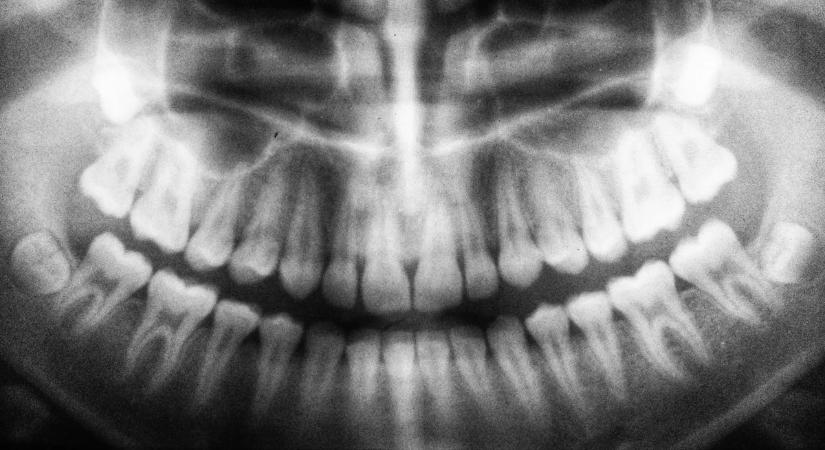

Fogfájásra panaszkodott a férfi, majd orvosa nem találta meg csontjait 2026.03.05. 11:00 Borsonline - Aktuális csont férfi A diagnózis hallatán teljesen ledöbbent. Elolvasom a cikket >> - Hirdetés -